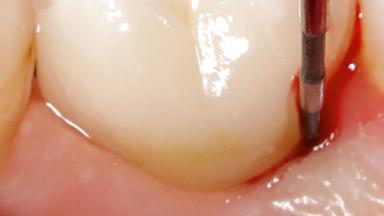

Treatment of Peri-Implantitis at a Zirconia Implant

Frank Schwarz, Ausra Ramanauskaite

Due to their promising clinical performance, zirconia implants have recently become popular alternatives to titanium implants, particularly for areas with high esthetic demands (Holländer and coworkers 2016; Roehling and coworkers 2016; Lorenz and coworkers 2019). However, regardless of the reported high survival and success rates, zirconia implants were affected by peri-implant diseases over the short observation period, suggesting the importance of treating peri-implant diseases at zirconia implants (Becker and coworkers 2017). In their case, Frank Schwarz and Ausra Ramanauskaite present 3-year results following mechanical debridement alongside Er:YAG laser monotherapy.